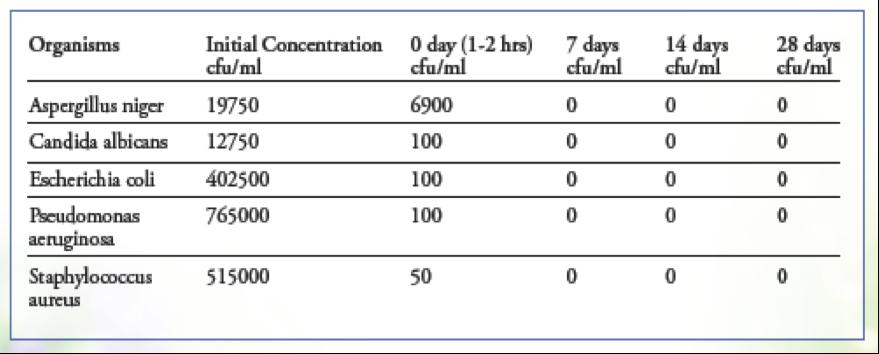

Using the anti-pathogenic properties of more than one botanical in a combination or formula provides a broader spectrum of activity against pathogens. e resulting formulations, or “biocidal combinations”, are powerful allies that may be used to address infection. Testing has illustrated remarkable broad-spectrum antimicrobial activity (in vitro) with a combination containing Bilberry extract, Noni, Milk istle, Echinacea (purpurea & angustifolia), Goldenseal, Shiitake, White Willow, Garlic, Grapeseed extract, Black Walnut (hull and leaf ), Raspberry, Fumitory, Gentian, Tea Tree oil, Galbanum oil, Lavender oil, and Oregano oil. A & L Analytical Laboratories, performed USP E ectiveness Tests, in which this botanical combination was injected with large numbers of disease causing organisms and then cultured for 28 days. e

results demonstrated the bacteria and yeast pathogens are completely eliminated in a matter of hours, and do not recur over a 28 day period of being cultured.

“ e advanced botanical combination appears to be e ective at reducing the level of inoculates.” - John Toth, Bio-Services, A & L Laboratories. BOTANICALS ARE EFFECTIVE AGAINST BIOFILMS